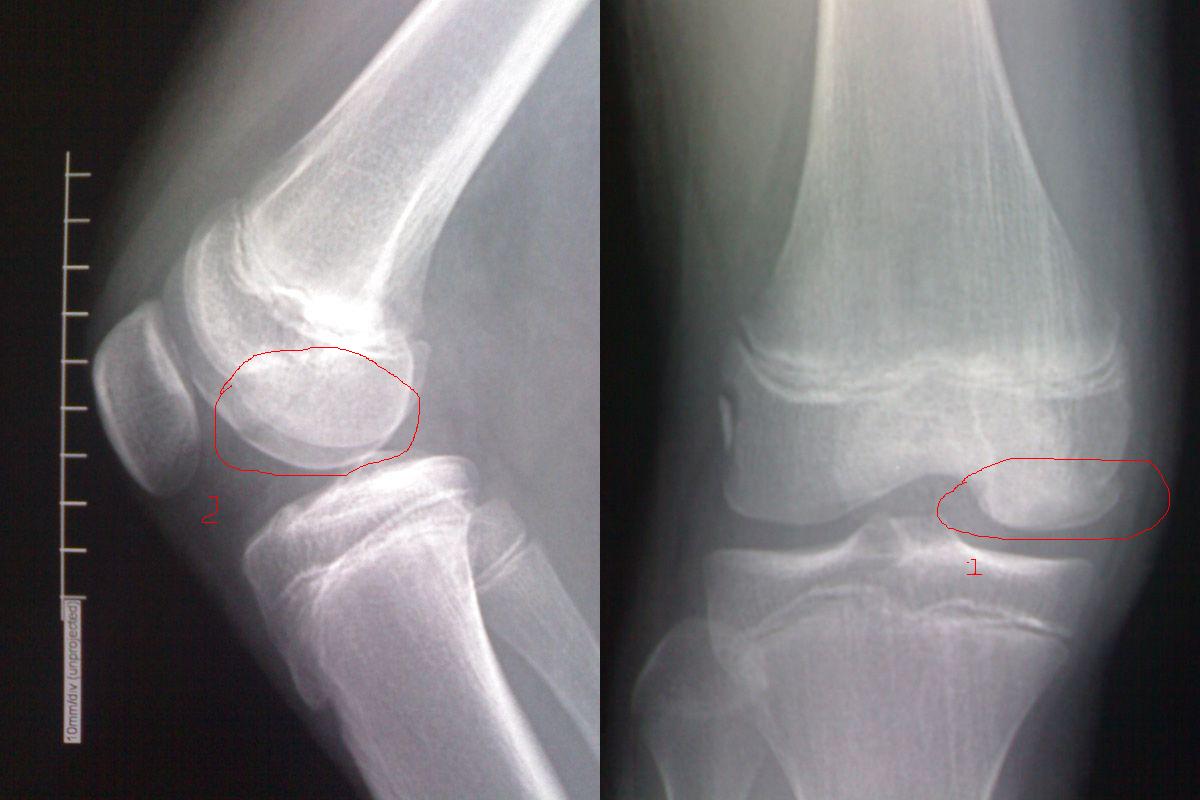

女,12岁。右膝关节车祸伤

右膝关节外侧髁边缘锐利的条片状高密度影,局部骨质缺损,局部软组织未见明显异常,不太支持骨折,考虑剥脱性骨软骨炎可能。

1、股骨内侧髁骨折;

2、外侧髁考虑永存骨骺。

1)右侧股骨内侧髁骨折波及关节面。2)考虑右侧股骨外侧髁剥脱性骨软骨炎,不排除永存骨骺。

剥脱性骨软骨炎为关节软骨及软骨下骨的无菌性坏死,并非正真炎症,又称kunig‘s病,好发青少年,男多于女,x线表现为关节面局限性骨质疏松区围绕一块相对致密骨片,形成一环形透明巢包含一块小死骨,碎片可形成游离体,脱落部分留有局部骨关节面的缺损凹陷,部分病变可由修复新骨形成而消失。

此例病变部位无关节面软骨覆盖,不应考虑剥脱性骨软骨炎,可考虑永存骨骺(二次骨化中心不愈合)。

股骨内髁骨折可以肯定,外髁是骨折、软骨炎还是永存骨骺?请结合临床详细查一查。